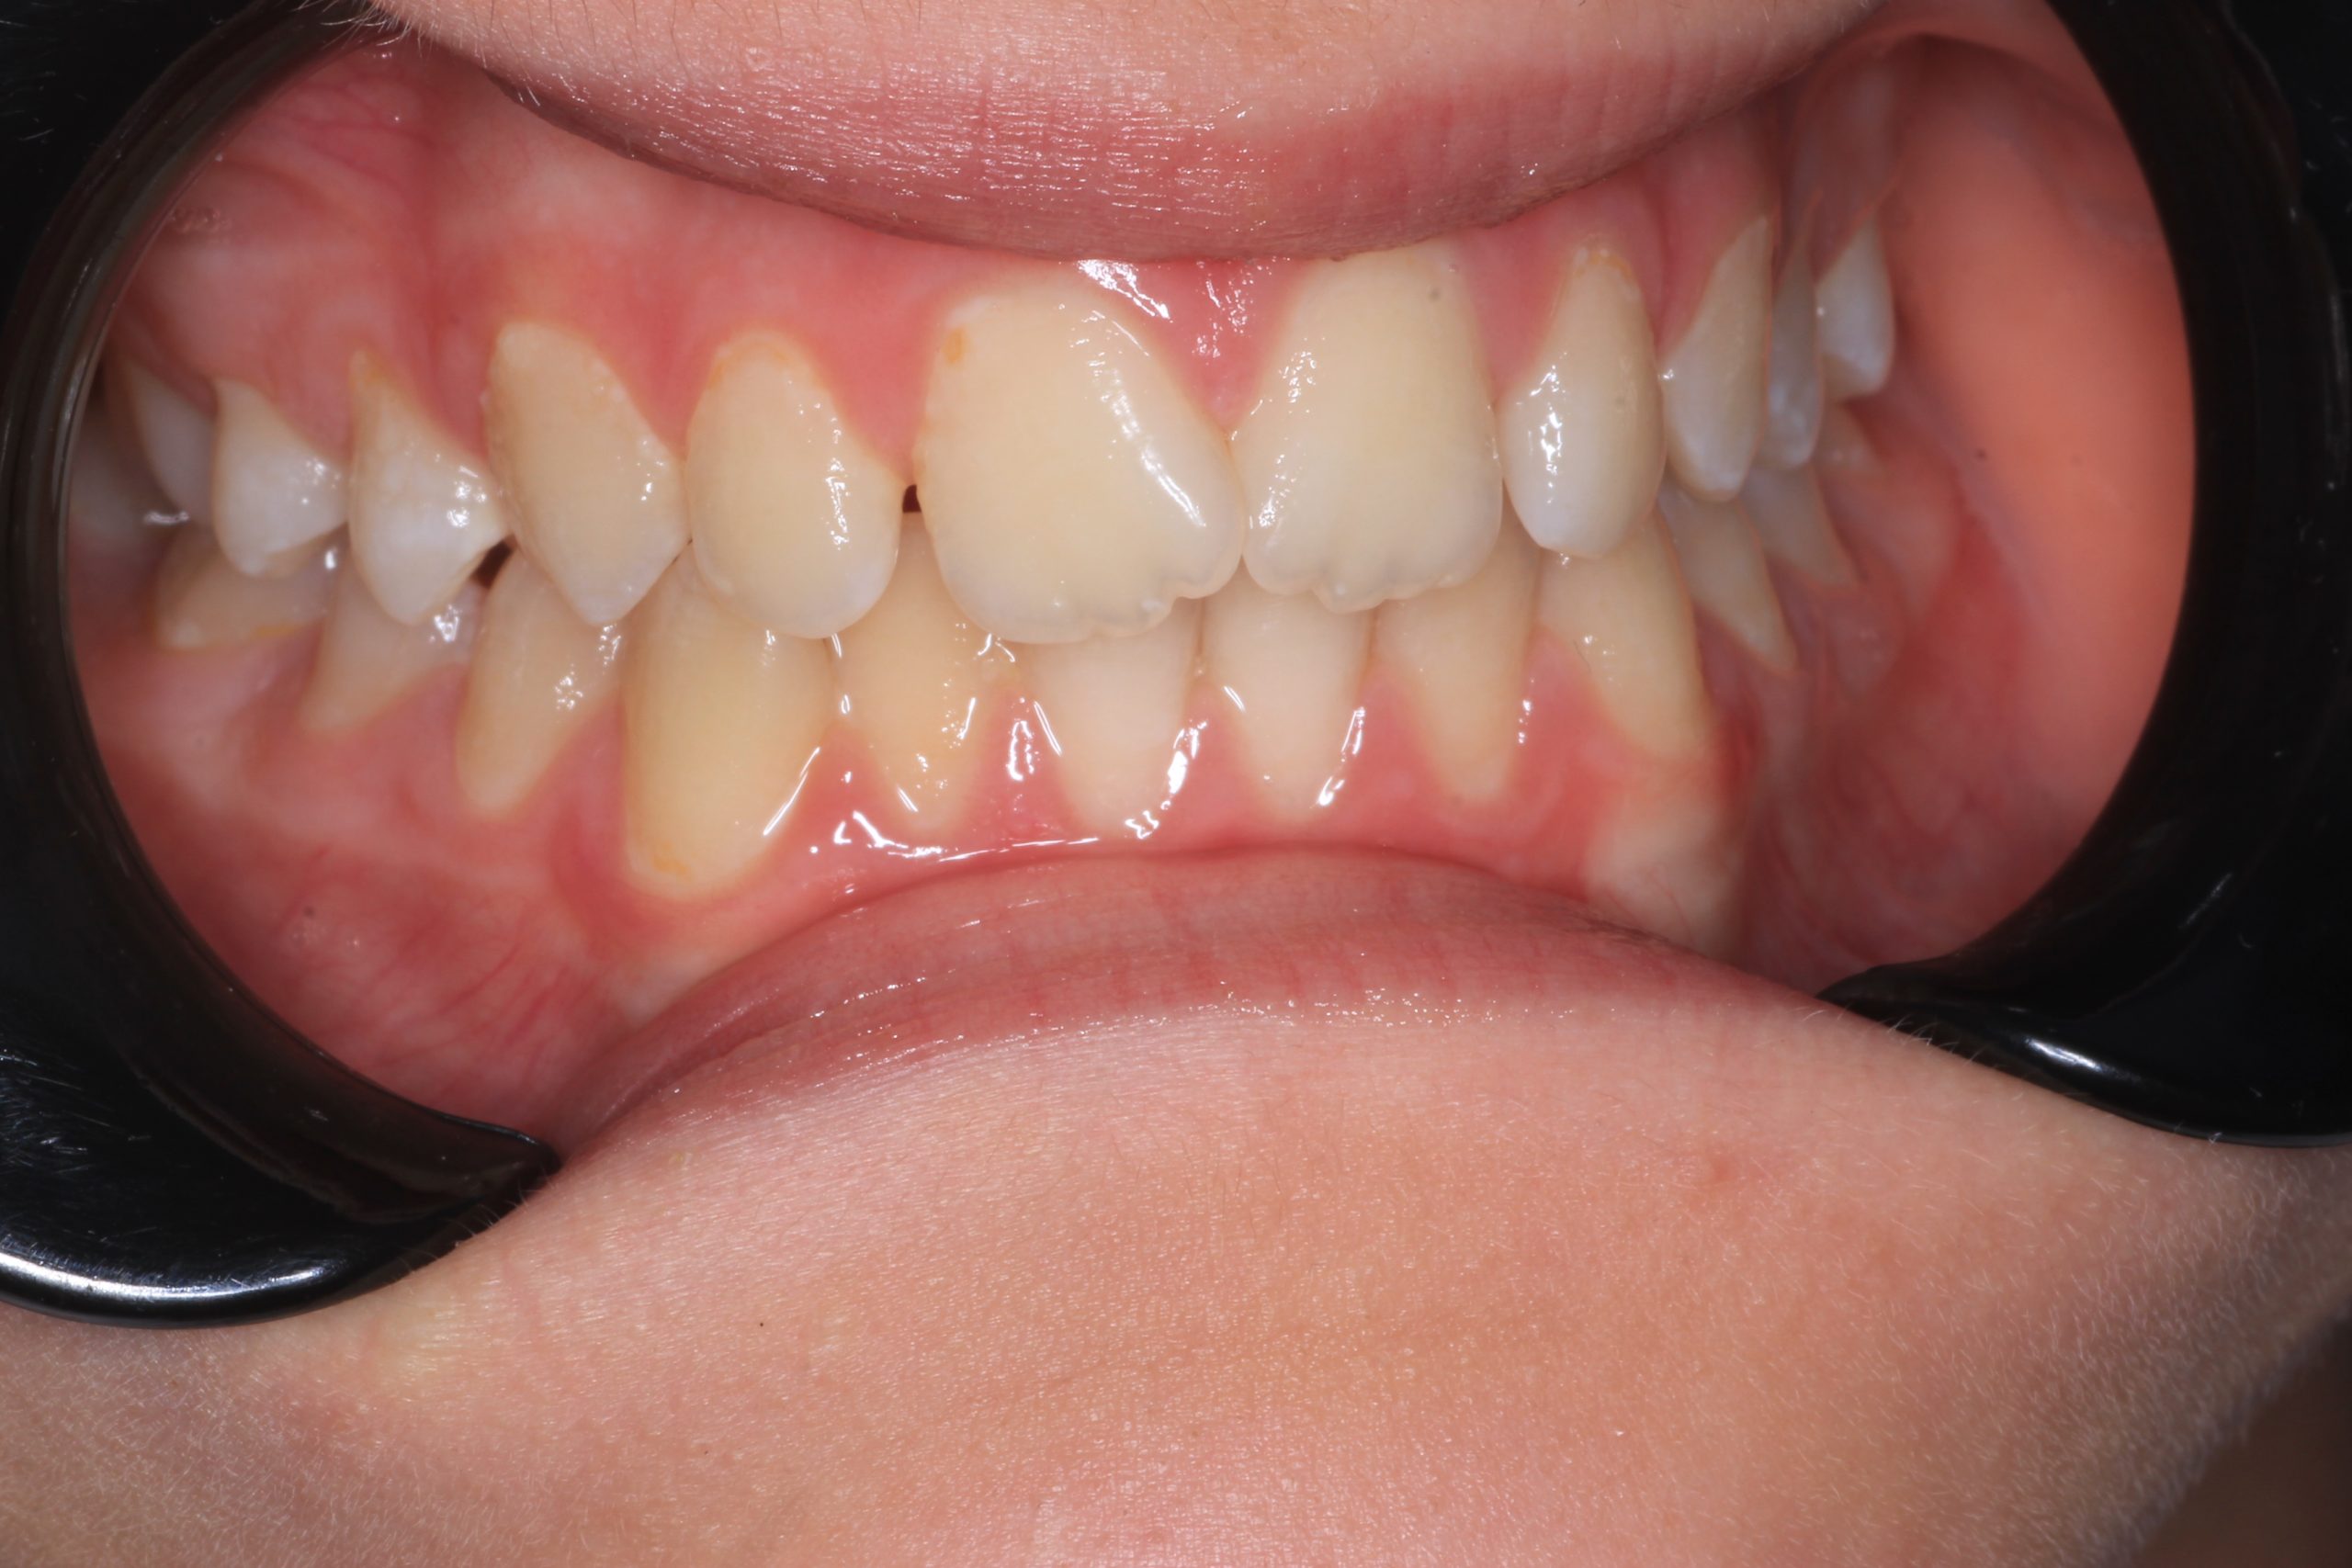

- Detailed Examination

We examine the condition of teeth, gums, and bite. - Plaque Disclosure with Special Indicators